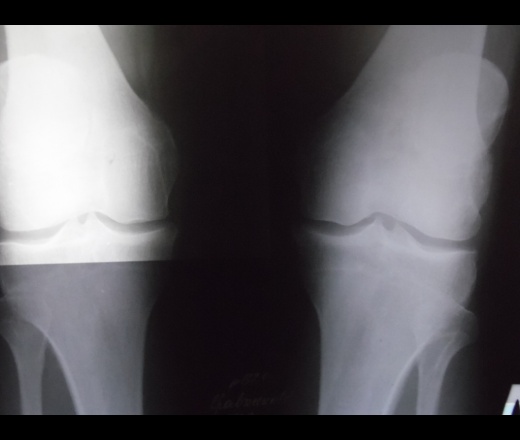

Сильно болит с внутренней стороны бедра и ягодицы и что то счёлкает с внутренней стороны бедра когда от воже ногу в сторону сильные боли в спине а также коленные суставы раскажите есть ли на снимках коксартроз и гонортроз и чем могут быть вызваны эти боли

а признаки артрозов есть)в коленках суставные щели сужены, межмыщелковые возвышения заострены. Слева у латерального края большеберцовай кажется намечается остеофит.

мне написали что коксортроза нету а гонортроз 1 степени

Может меня сейчас забросают тапками за гипердиагностику, но я вижу изменения в правом тазобедренном. Но МРТ поясничного отдела позвоночника все же сделайте.

Начальнейшие, я бы даже сказал зачаточные, признаки гон-коксартроза.

с какой стороны боли, сколько лет... Но с обеих сторон ренгенологическая картина одинакова, суставные щели не сужены, ничего особенного нет.

На представленных рентгенограммах ничего страшного не вижу. Есть небольшой перекос таза влево, который может быть вызван перекосом позвоночника. Нужен хороший доктор, чтобы выслушать жалобы пациента, осмотреть и ощупать, а потом назначать необходимые исследования. Если начинать с рентгенограмм всего тела, то причина болезни может ускользнуть. Возможно, нужно прислущаться к советам умных людей и обследовать поясничный отдел позвоночника. Но только после осмотра врача!